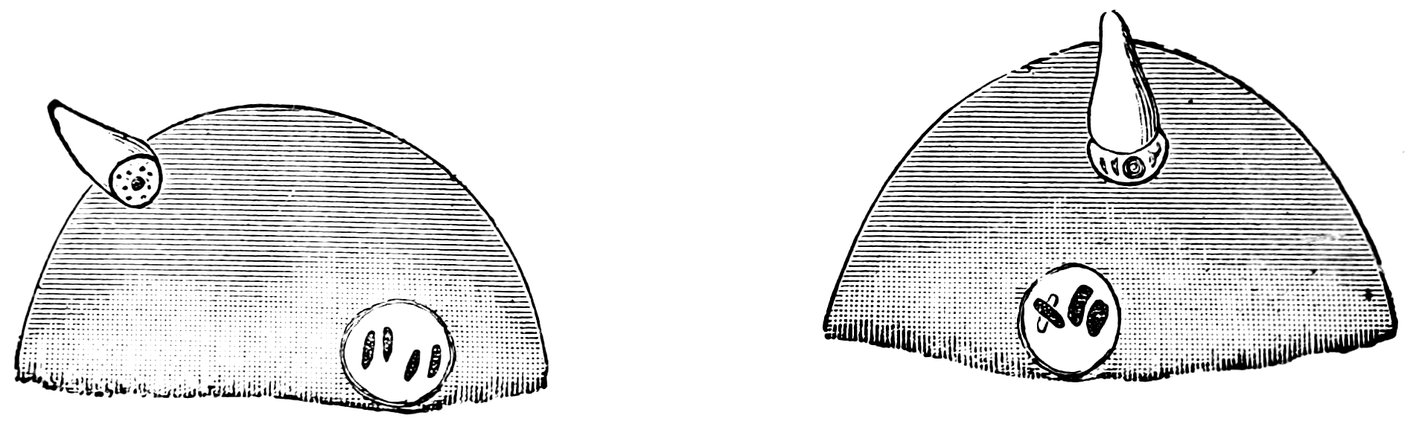

| 18. | Annular Hymen | 64 |

| 19. | Annular Hymen | 64 |

| 20. | Semilunar Hymen | 65 |

| 21. | Annular Hymen with Congenital Symmetrical Indentations | 65 |

| 22. | Fimbriate Hymen | 65 |

| 23. | Deflorated Fimbriate Hymen | 65 |